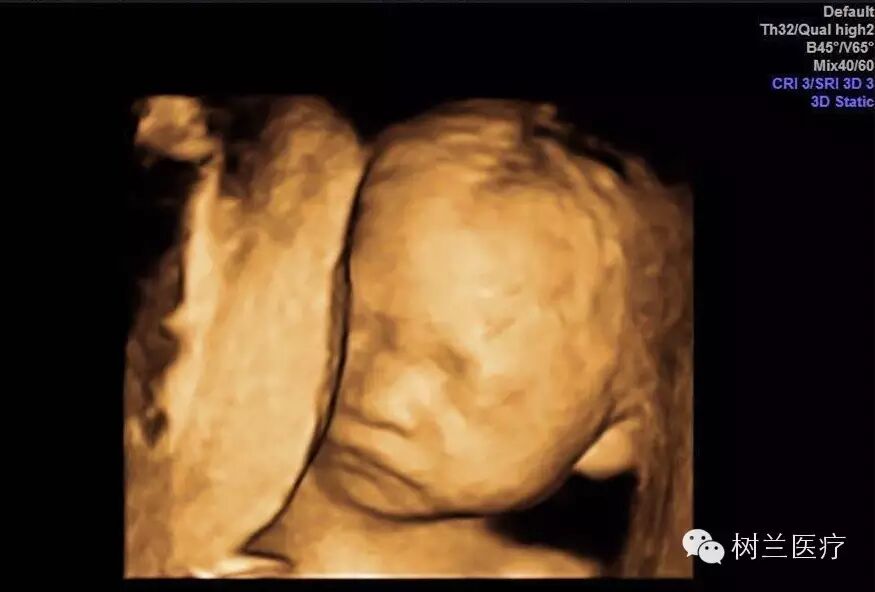

妈妈和宝宝的第一次互动

不是胎动的那一刻

也不是出生时的那个依偎

而是在四维彩超中

看到的那一眼

陈女士的宝宝很活泼,影像下可见他(她)一会噘嘴、一会动鼻子,好像在向大家打招呼。

宝宝的健康是妈妈最大的牵挂,据了解,我国每年约有80-120万缺陷儿出生,而四维彩超筛查作为预防新生儿出生缺陷的重要防线,通过4D超声图像加上时间的维度参数,可以动态监测宝宝的生长发育情况,对胎儿畸形,如唇裂、腭裂、骨骼发育异常、心血管畸形等能早期诊断。